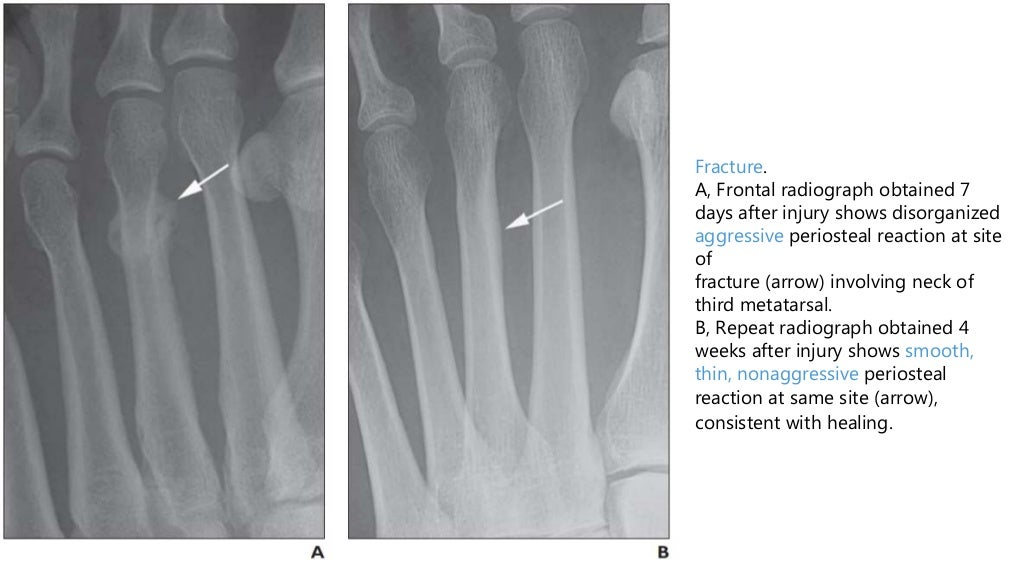

From www.ajronline.org

Periosteal Reaction AJR Types Of Periosteal Reaction Periosteal reactions may be classified as benign or aggressive (note: there are multiple types of periosteal reaction, divided into nonaggressive types (thin, thick irregular,. periosteal reaction results when cortical bone reacts to one of many possible insults. Smooth, solid or thick, and aggressive. types of periosteal reaction there is confusing overlap in the literature regarding the terminology. Types Of Periosteal Reaction.

Periosteal Reaction AJR Types Of Periosteal Reaction periosteal reaction results when cortical bone reacts to one of many possible insults. periosteal reaction may also be grouped into several patterns: Smooth, solid or thick, and aggressive. Tumor, infection, trauma, certain drugs, and some arthritic conditions. Not benign and malignant) based on the time. periosteal reaction refers to the elevation of periosteum from cortical bone and. Types Of Periosteal Reaction.

Periosteal Reaction AJR Types Of Periosteal Reaction periosteal reaction refers to the elevation of periosteum from cortical bone and the subsequent deposition of new bone in this. Smooth, solid or thick, and aggressive. types of periosteal reaction there is confusing overlap in the literature regarding the terminology used to describe. Tumor, infection, trauma, certain drugs, and some arthritic conditions. there are multiple types of. Types Of Periosteal Reaction.

Periosteal Reaction AJR Types Of Periosteal Reaction Tumor, infection, trauma, certain drugs, and some arthritic conditions. periosteal reaction refers to the elevation of periosteum from cortical bone and the subsequent deposition of new bone in this. periosteal reaction may also be grouped into several patterns: periosteal reaction results when cortical bone reacts to one of many possible insults. types of periosteal reaction there. Types Of Periosteal Reaction.

Periosteal Reaction AJR Types Of Periosteal Reaction periosteal reaction results when cortical bone reacts to one of many possible insults. Periosteal reactions may be classified as benign or aggressive (note: types of periosteal reaction there is confusing overlap in the literature regarding the terminology used to describe. Not benign and malignant) based on the time. Smooth, solid or thick, and aggressive. Tumor, infection, trauma, certain. Types Of Periosteal Reaction.

Periosteal Reaction AJR Types Of Periosteal Reaction periosteal reaction results when cortical bone reacts to one of many possible insults. Tumor, infection, trauma, certain drugs, and some arthritic conditions. there are multiple types of periosteal reaction, divided into nonaggressive types (thin, thick irregular,. Periosteal reactions may be classified as benign or aggressive (note: Not benign and malignant) based on the time. types of periosteal. Types Of Periosteal Reaction.

Periosteal Reaction AJR Types Of Periosteal Reaction Smooth, solid or thick, and aggressive. periosteal reaction may also be grouped into several patterns: Periosteal reactions may be classified as benign or aggressive (note: Tumor, infection, trauma, certain drugs, and some arthritic conditions. periosteal reaction results when cortical bone reacts to one of many possible insults. types of periosteal reaction there is confusing overlap in the. Types Of Periosteal Reaction.

Periosteal Reaction AJR Types Of Periosteal Reaction Not benign and malignant) based on the time. Smooth, solid or thick, and aggressive. Tumor, infection, trauma, certain drugs, and some arthritic conditions. Periosteal reactions may be classified as benign or aggressive (note: types of periosteal reaction there is confusing overlap in the literature regarding the terminology used to describe. periosteal reaction refers to the elevation of periosteum. Types Of Periosteal Reaction.